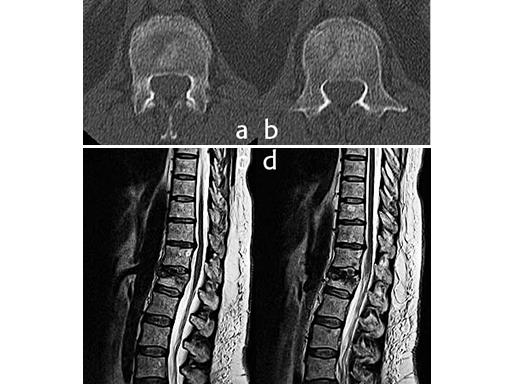

Additionally, a MRI scan was performed to analyze the integrity of the soft tissue in detail. The lateral MRI clearly showed a ruptured intervertebral disc at the level T12/L1.

Using the USS Fracture MIS system for the initial stabilization allowed for a minimally invasive approach with intraoperative active reduction of the spinal fracture. The unique design of the fracture clamp allowed for independent correction of the sagittal alignment (Fig a) as well as height readjustment (Fig b).

For this patient, independent lordosis correction, height readjustment, and spinal stabilization were the primary goal of surgery. As percutaneous toploading pedicle screw systems cannot provide independent correction of the flexion-compression deformity, the fracture clamps and Schanz screws of the USS Fracture MIS system were used to overcome this disadvantage.